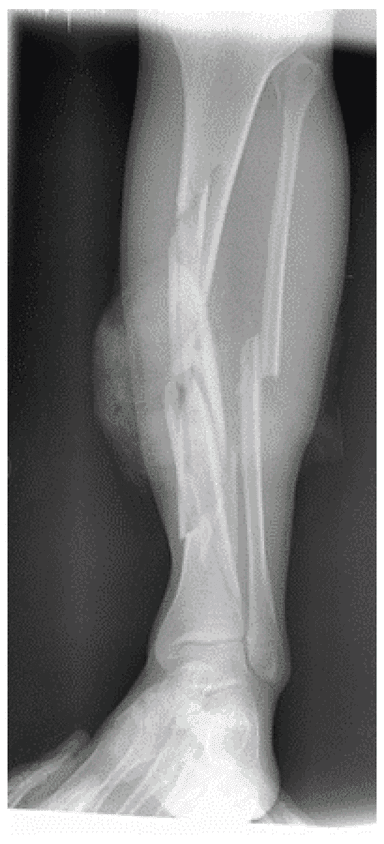

Зображення 5. Використання апарата зовнішньої фіксації для стабілізації нижньої кінцівки після вибухової травми

На базовій рентгенограмі, отриманій перед процедурою, видно осколкові переломи у дистальній третині стегнової кістки та середній ділянці тіла великогомілкової кістки. Над колінним суглобом було розташовано апарат зовнішньої фіксації, тоді як розширений зовнішній фіксатор у вигляді «дельтоподібної рами» використовує замок стержня у проксимальній ділянці великогомілкової кістки для стабілізації сегментарного перелому великогомілкової кістки.

Зобр. 5a. Осколковий перелом дистального відділу стегнової кістки

Зобр. 5b. Переломи середньої ділянки тіла великогомілкової кістки